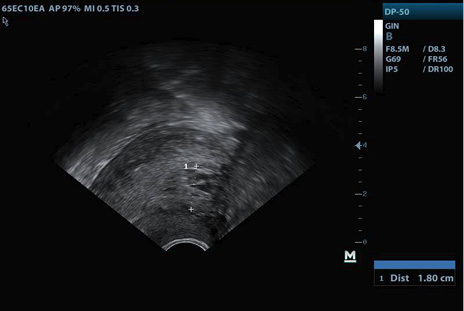

La evolución en controles subsiguientes evidenció persistencia del sangrado genital y dolor pélvico, sin signos de infección, endometrio ecográficamente mixto sin disminución de grosor (Figuras 2-3), y niveles de GCH en descenso lento, por lo que a los 28 días después de la expulsión se decidió prueba terapéutica con misoprostol dosis única vaginal, sin éxito.